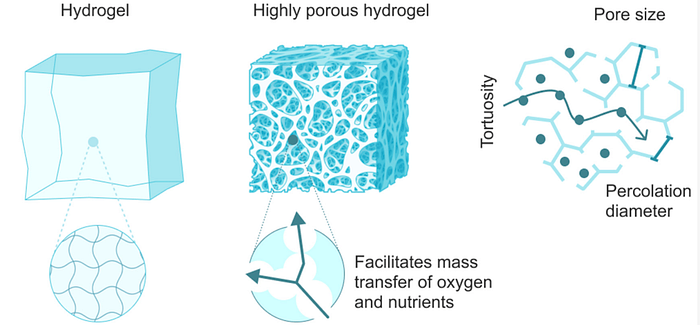

A nanogel is a polymer-based, crosslinked hydrogel particle on the sub-micron scale. It essentially combines the advantages of a hydrogel with nanoparticles. To understand nanogels we must first understand hydrogels. A hydrogel is a three-dimensional network formed by hydrophilic polymers through chemical (covalent or ionic bonds) or physical (hydrogen bonds, van der Waals force, physical entanglement) cross-linking. Hydrogels can swell (enlarge) and retain a significant fraction of water within their structure, but they will not dissolve in water. It is produced by the simple reaction of one or more monomers: a molecule that can be bonded to other identical molecules to form a polymer. Think of hydrogels as essentially a gel: they are stable yet still possess a fluid and free-flowing quality.

Now that we understand the importance of hydrogels, lets return to nanogels. A nanogels characteristics, such as size, charge, porosity, amphiphilicity, softness, and degradability, can be fine-tuned by varying their chemical composition. They can be designed in a spherical shape or in a more porous structure, with holes in their shape. From a drug delivery perspective, this essentially allows us to design the system based on how we want the drug to be released. Based on the structure, drugs can be released in different orders. For example, in a spherical shape, the outermost contained drug would be released first; however, in a porous structure, you could theoretically have the innermost structure released first. The porous structure is sort of like Swiss cheese in that there are ways to get to the middle of the structure, allowing you to theoretically release drugs from the inside out.